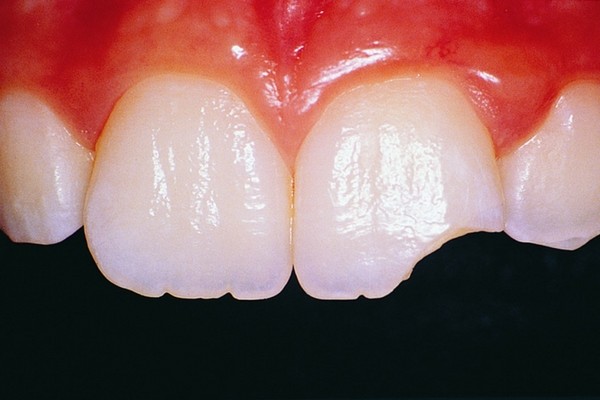

Will my chipped tooth go black?

If the chip in your tooth is just in the enamel (the hard outer layer of your tooth) then, so long as you keep the tooth clean, the chances are it will not go black. There is no need to see a dentist urgently, simply make an appointment at your earliest convenience to discuss how this can be repaired.

If the chip in your tooth goes through the enamel and into the dentine (the softer part of your tooth) then the dentine may pick up stains more readily and go dark. Because the dentine is softer, it will also be more prone to dental decay causing a black tooth. You should see a dentist about this; however, it would not be considered an emergency appointment unless it is accompanied by pain.

If the chip goes all the way through the enamel, dentine and down to the pulp (the living blood supply part of your tooth) this will more than likely be extremely painful and you may even see blood from the chip. If this is left untreated, not only could you be in extreme pain but the tooth could begin to die and will almost certainly go black. You will need to see an emergency dentist as soon as possible.